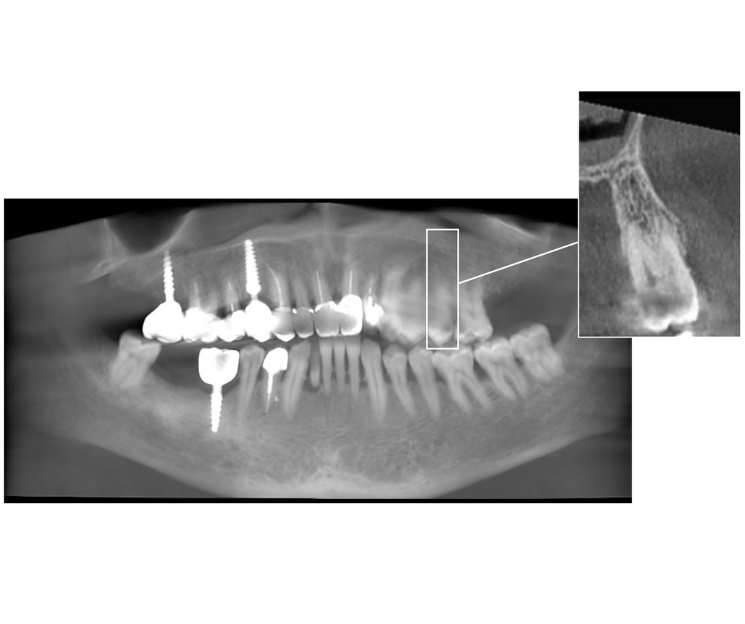

Se optó por un implante monofásico compresivo. La indicación se basó en dos criterios fundamentales:

- Volumen óseo adecuado: Existencia de un lecho receptor con hueso sano.

- Búsqueda de estabilidad primaria: Este tipo de implante permite condensar el hueso esponjoso durante la inserción, aumentando su densidad y logrando una excelente estabilidad primaria, requisito indispensable para la rehabilitación inmediata.